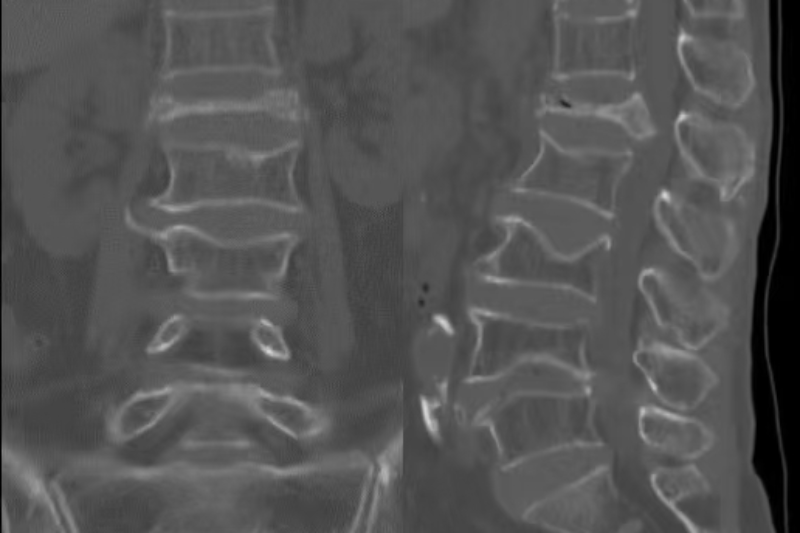

術前CT